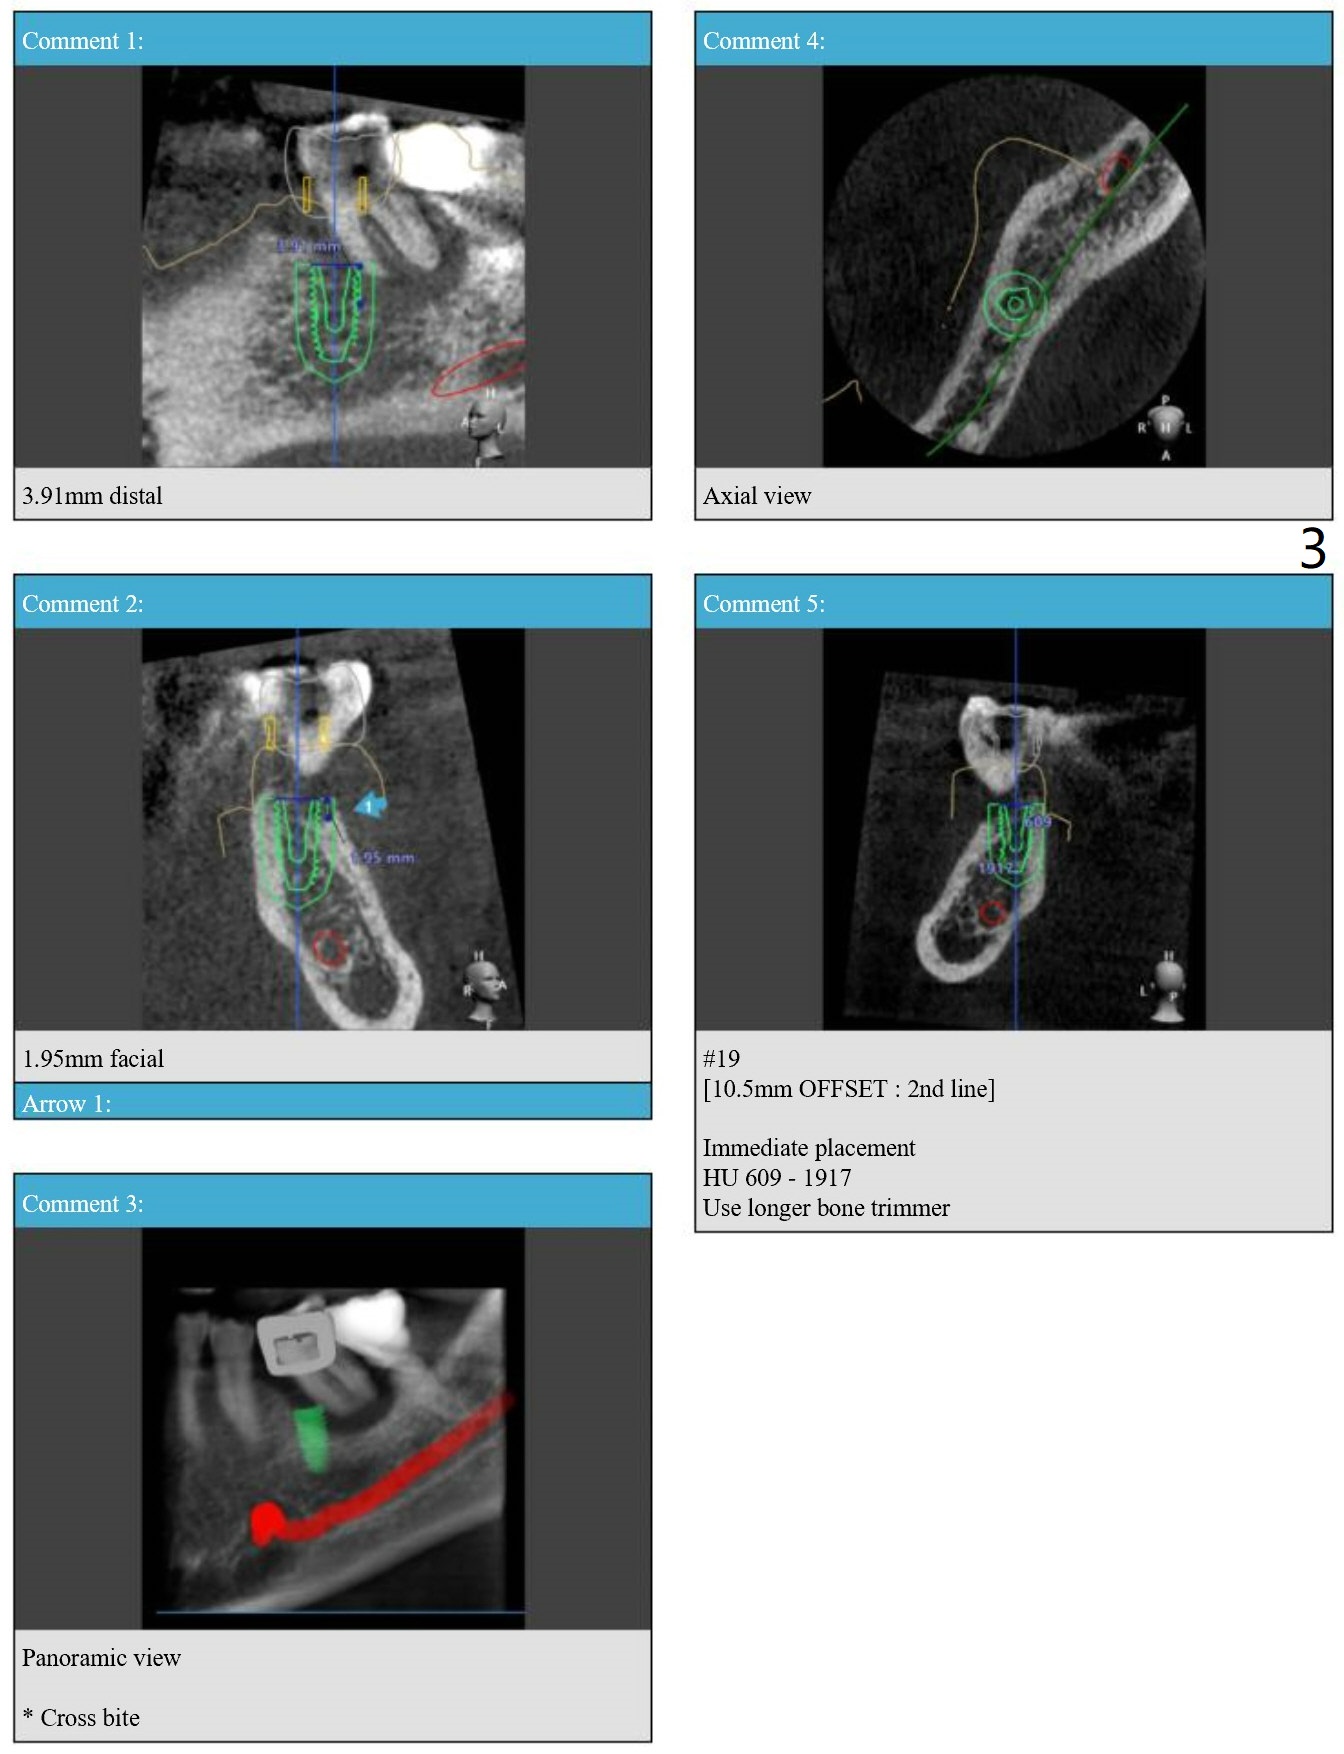

As Lingual As Possible  M

Return to Lower Molar Immediate Implant, Prevent Molar Periimplantitis (Protocols, Table), Trajectory, Weichat